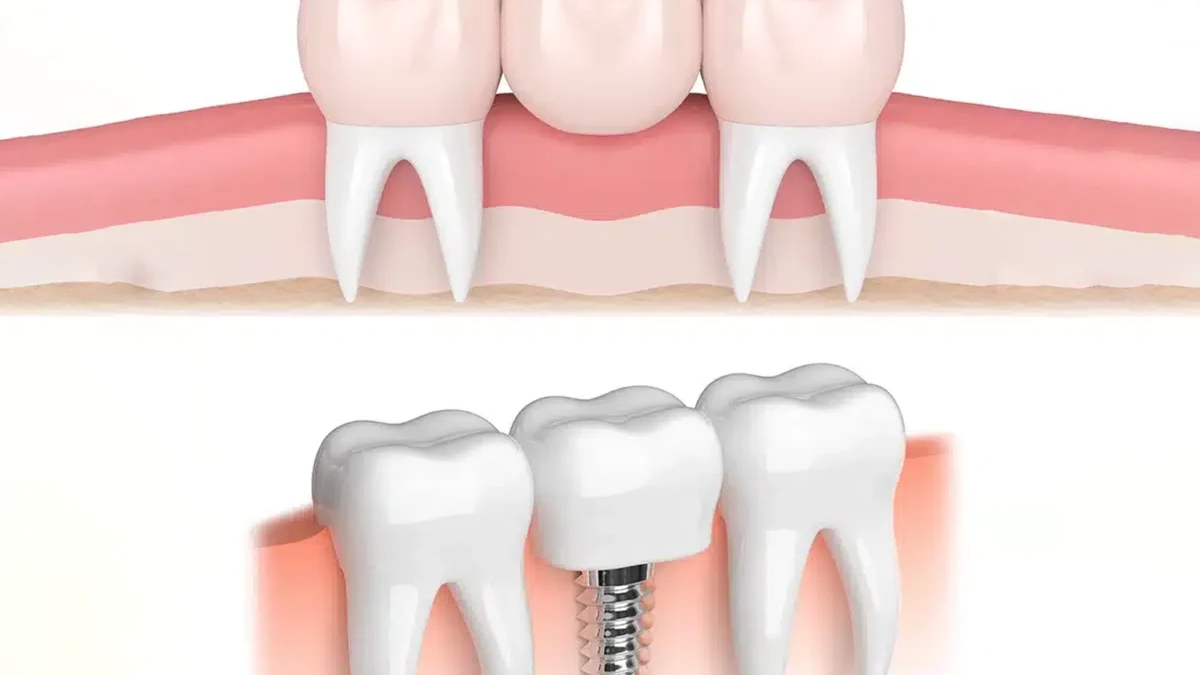

Dental implants are artificial tooth roots, usually made of titanium, that are surgically placed into the jawbone. Once the implant fuses with the bone—a process called osseointegration—a crown is attached on top, creating a natural-looking and functional tooth. Implants are designed to last for decades, often a lifetime, with proper care.

Dental bridges are restorations that replace one or more missing teeth by anchoring a false tooth (pontic) to the adjacent natural teeth. The supporting teeth are typically prepared by removing some enamel to fit crowns, which hold the bridge in place. Bridges have been used for decades as a reliable tooth replacement option.